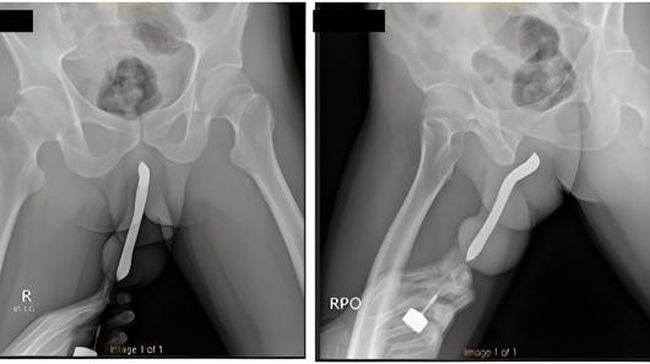

Pria di Jatim masukkan sikat gigi ke penis (Foto: International Journal of Surgery Case Reports)

Kasus pasien ini dipublikasi jurnal medis internasional. Kasus yang dipublikasikan di International Journal of Surgery Case Reports menyebut pria itu ke rumah sakit setelah sikat gigi yang ditancapkan ke alat vitalnya itu patah menjadi dua saat dia berhubungan seks.